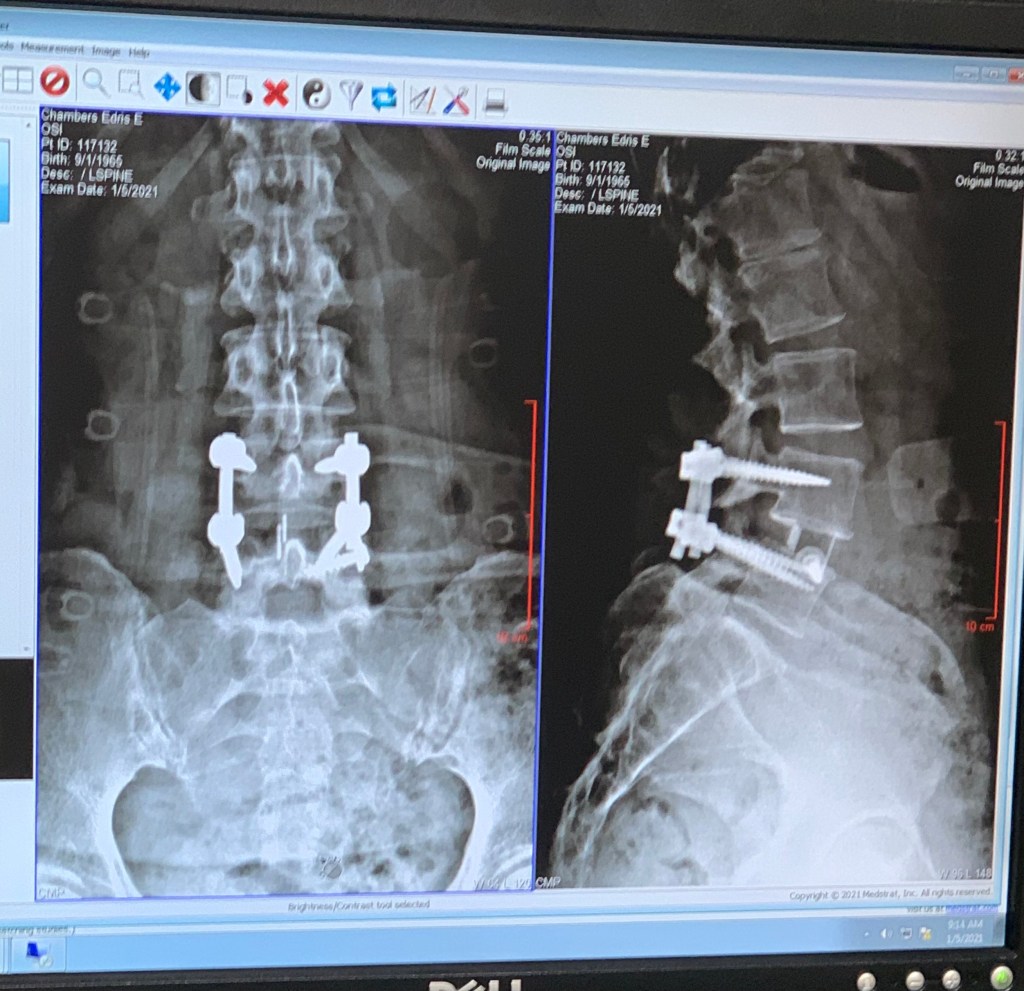

I have a scar on my neck from a blown disc, a scar around my knee from a torn meniscus root, a scar on my foot from another repair, and a couple of scars on my back and side from a laminectomy & fusion. The visible scars have an explanation. It’s the hidden scars that are hard to explain.